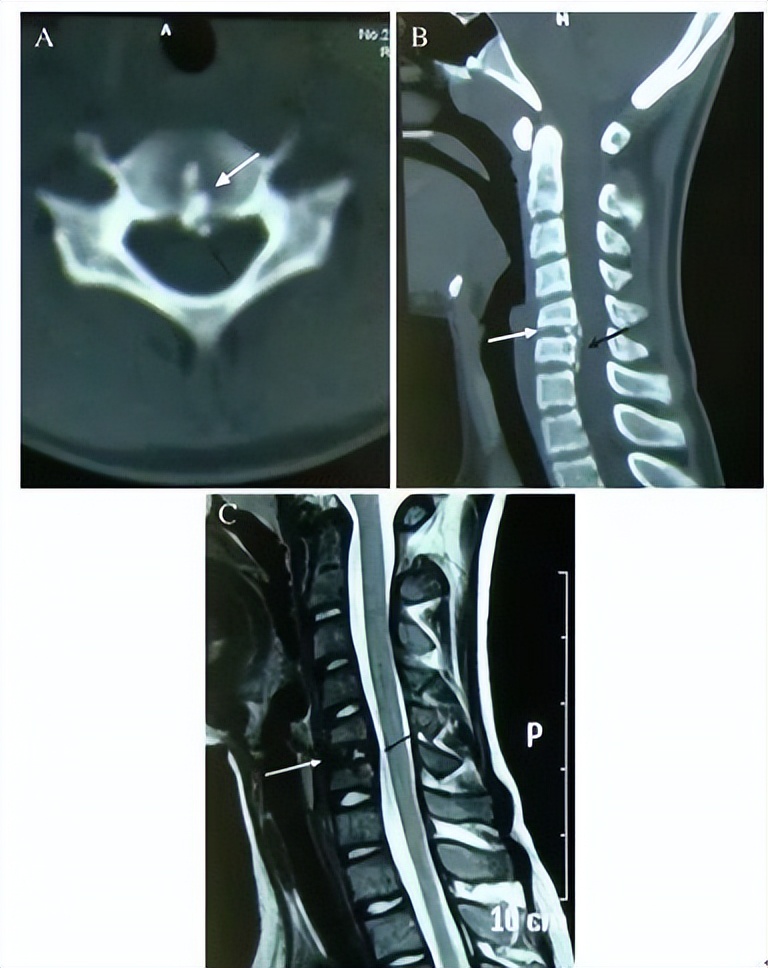

明确诊断主要通过影像学方法,颈椎CT是关键。颈长肌钙化性肌腱炎特异性的影像表现是C1-4椎体前缘软组织肿胀和积液与C1椎体前弓下方不规则钙化沉着共存。

图:C1椎体前弓下方不规则钙化沉着

图:椎前积液

图:椎前积液和C1椎体前弓下方不规则钙化沉着

图:椎前软组织肿胀